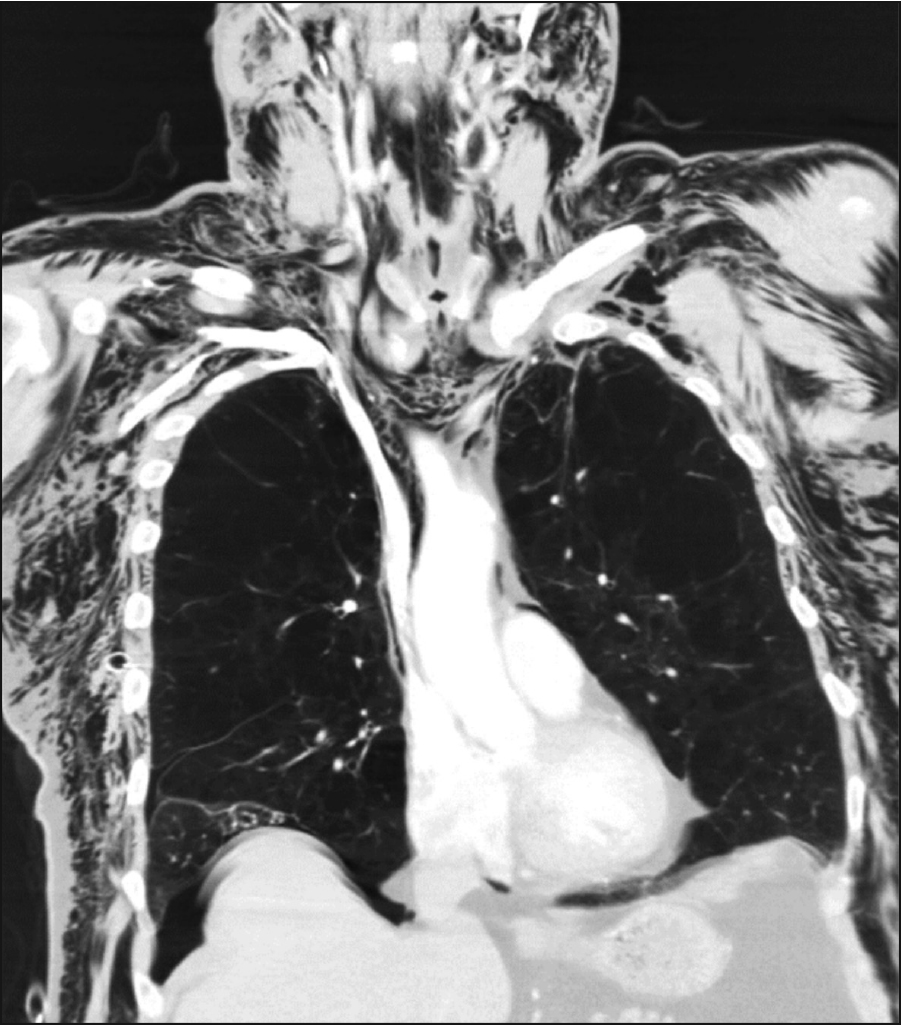

Figure 3. CT scan showing subcutaneous emphysema

Figure 3. CT scan showing subcutaneous emphysema(click to enlarge)

This is a case of a 75-year-old man with severe smoking related COPD who presented with a secondary pneumothorax. Attempts to treat a persistent air leak using intercoastal (IC) drains of increasing size led to sudden worsening of iatrogenic subcutaneous emphysema. A CT scan performed confirmed the presence of a pneumomediastium and florid subcutaneous emphysema in the face and torso (see Figure 3). Although the patient reported a change in voice with hoarseness there was no evidence of airway compromise. The patient was conservatively managed in the high-dependency unit. He was not considered fit enough to undergo general anaesthesia and surgery; therefore, a pleurodesis using sterile talc was undertaken. The IC drain was successfully removed, following resolution of the air leak and the lung remained re-inflated. His subcutaneous emphysema gradually spontaneously resolved with no further complications.